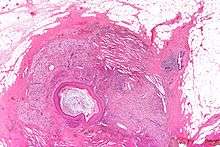

Squamous metaplasia of lactiferous ducts

Squamous metaplasia of lactiferous ducts - abbreviated SMOLD is a change where the normal double layer cuboid epithelium of the lactiferous ducts is replaced by squamous keratinizing cell layers. The resulting epithelium is very similar to normal skin, hence some authors speak of epidermalization. SMOLD is rare in premenopausal women (possibly 0.1-3%) but more frequent (possibly up to 25%) in postmenopausal women where it does not cause any problems at all.

The last section of the lactiferous ducts is always lined with squamous keratinizing epithelium which appears to have important physiological functions. For example, the keratin forms plugs sealing the duct entry and has bacteriostatic properties. In SMOLD the keratinizing lining which is supposed to form only the ends of the lactiferous ducts extends deep into the ducts.